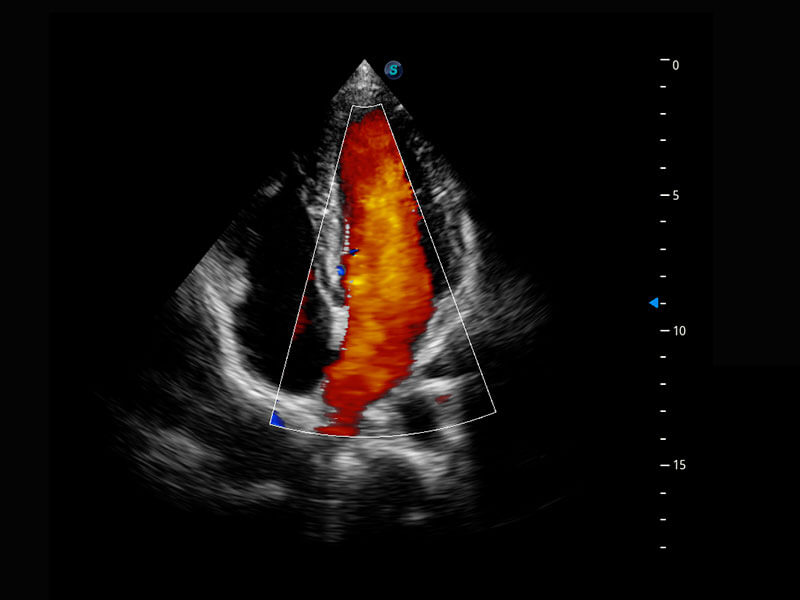

P60搭載寬頻帶線陣探頭、寬景成像、彈性成像技術(shù),為您提供乳腺應(yīng)用方案。P60支持高頻相控陣探頭、線陣探頭、腹部高頻探頭、腹部微凸探頭等,豐富的探頭群搭載敏感的彩色血流成像,適用于新生兒多種臟器檢測要求,滿足新生兒篩查需求。

新生兒心臟